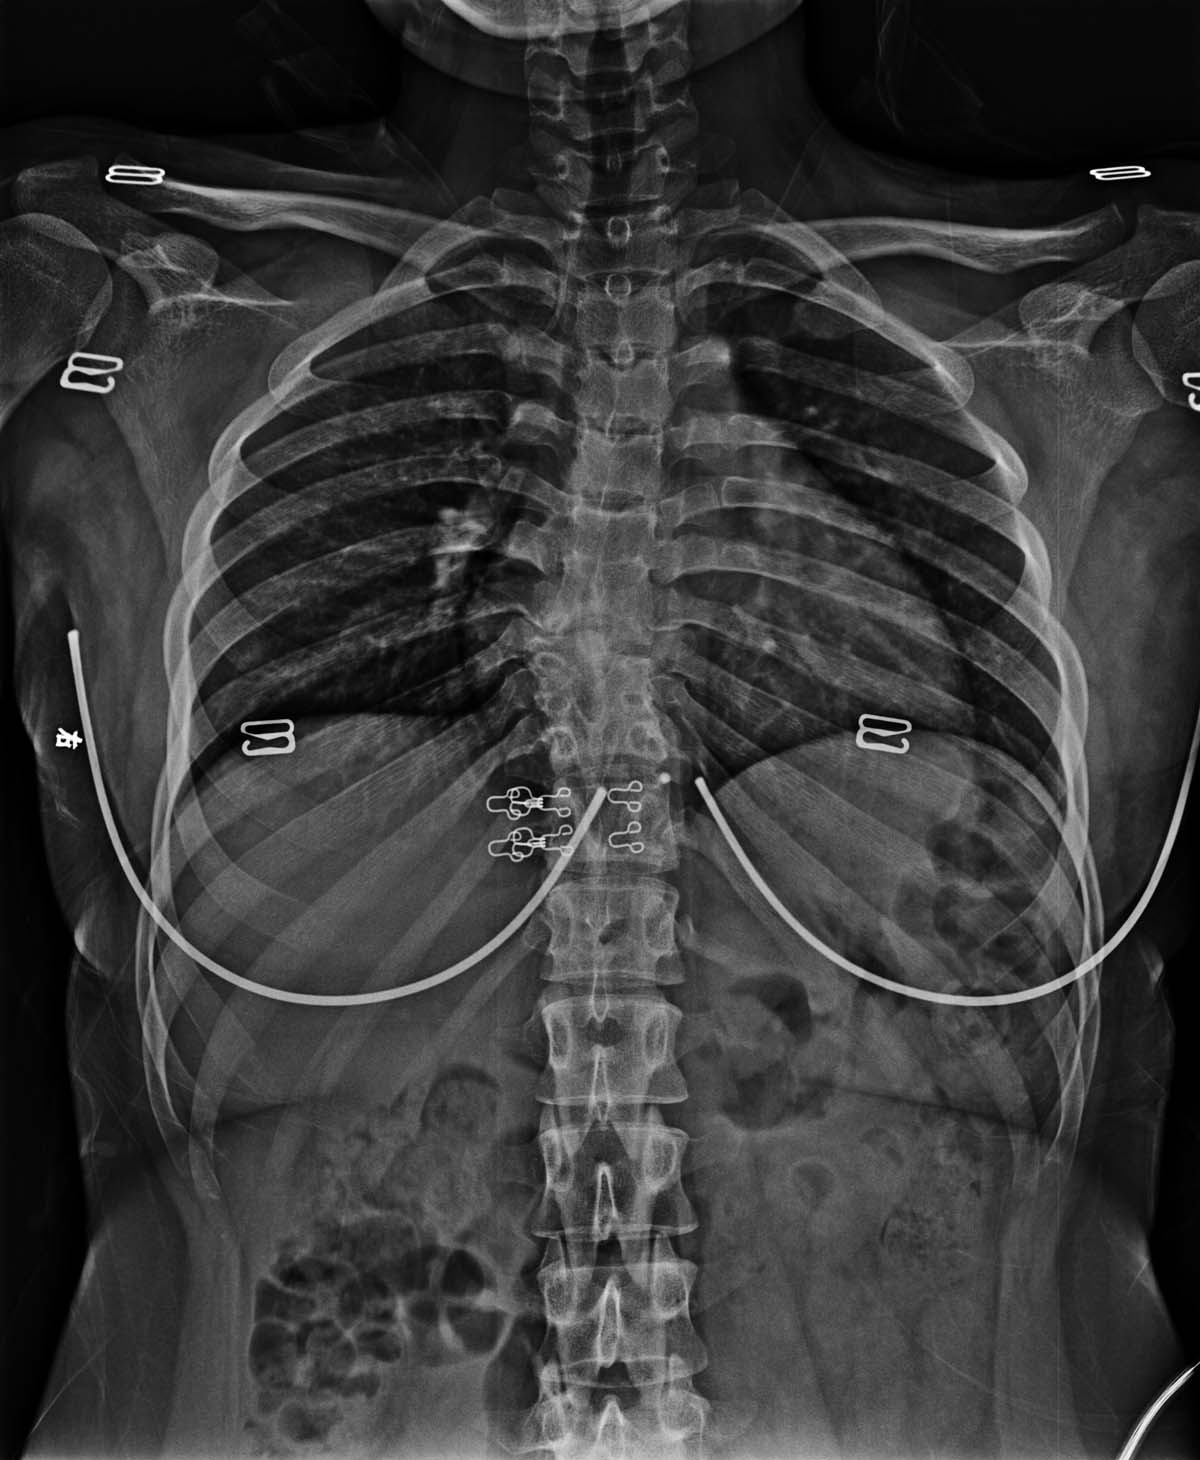

标题: X2233:胸椎结核是否活动?

女,19岁,2岁时胸椎结核,无手术,服药后愈合。具体不详。现背部痛。胸椎结核是否活动?

x光片提供资料不是很多

确实平片提供的信息太少,不好说病变是否稳定。